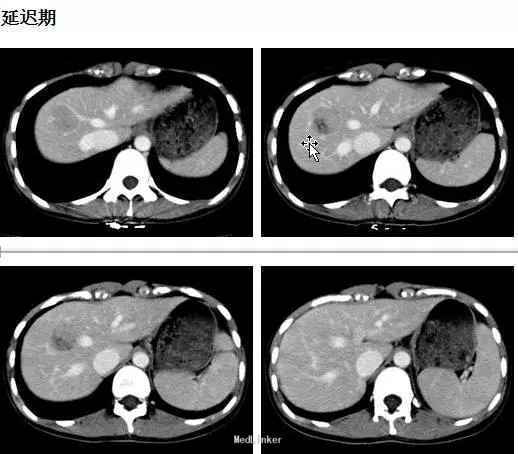

体检:腹平软,无肠型及蠕动波,未见腹壁静脉曲张,肝脾肋下未及,肝区无叩击痛,全腹无压痛、反跳痛、肌紧张。腹水征阴性。 CT表现:肝右前叶可见类圆形等低混杂密度影,边界尚清,直径约2.5cm,CT值-20~35HU,;增强后动脉期病灶呈结节样强化,门脉期病灶包膜强化更明显,有逐渐向中心填充趋势。

初步诊断:肝血管瘤。原拟定期复查,但患者强烈要求手术治疗,遂予肝部分切除术,术中所见也考虑血管瘤可能,术后恢复可。术后病理: 肝脏血管平滑肌脂肪瘤。免疫组化: melan-A(+)、HMB-45(+)、SMA灶性(+)、actin灶性(+)、S-100(-)、CK(-)、Desmin(-)、Ki-67阳性细胞约2%。

肝脏血管平滑肌脂肪瘤(HAML) 为一种罕见的肝脏间质性肿瘤, 由不同比例的血管、平滑肌和脂肪构成,1976 年Ishak首次报道本病。其发病机制尚不清楚,女性多见,以右叶居多。大多数患者无明显临床症状,多有体检发现。讨论:像本例患者有无必要手术,对于血管平滑肌脂肪瘤,手术指征如何?